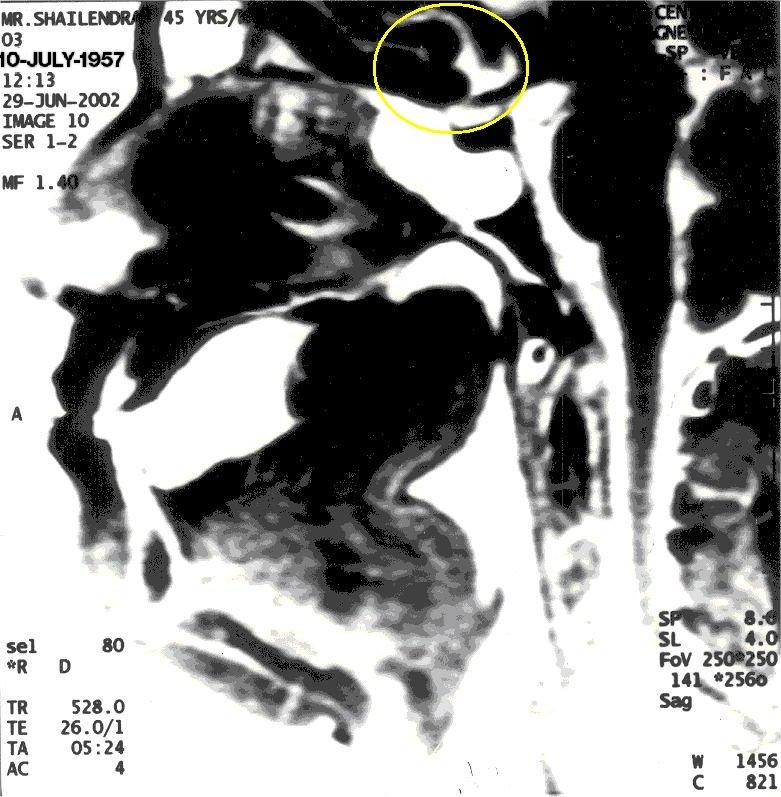

Performing Khechari Mudra

With Khechari Mudra, notice the formation of an 'Om' like impression (highlighted in yellow)